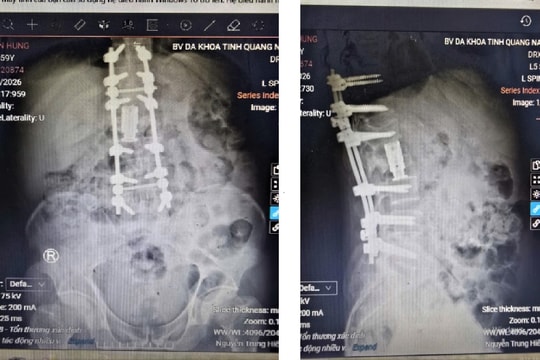

Phẫu thuật hai lối cứu bệnh nhân gãy cột sống phức tạp

ĐNO - Các bác sĩ Khoa Ngoại thần kinh - cột sống, Bệnh viện Đa khoa Quảng Nam vừa thực hiện thành công ca phẫu thuật cột sống hai lối cho bệnh nhân bị gãy cột sống thắt lưng kèm thoát vị đĩa đệm nhiều tầng, giúp người bệnh phục hồi vận động sau vài ngày.